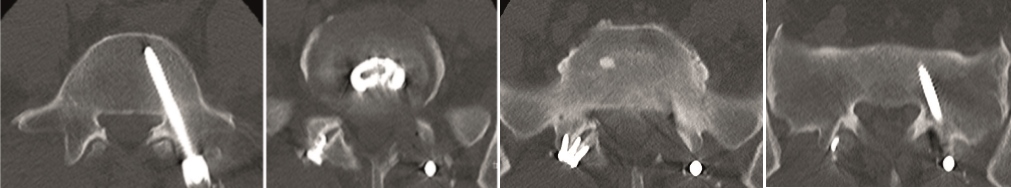

Multilevel facet pathology is shown in Fig 6. Intraoperative and postoperative images are shown (Fig 7-9).

A 40-year-old man 5 years after ALIF L4-L5 using SynFix with axial low back pain. The CT scan shows locked pseudarthrosis (Fig 17). Nonoperative treatment failed. The treatment option was bilateral Facet Wedge at L4-L5.

A less invasive approach was used with Insight Retractor using the bilateral Facet Wedge. No bone graft. X-ray follow-up after 3 months and CT assessment after 6 months (Fig 18-19).